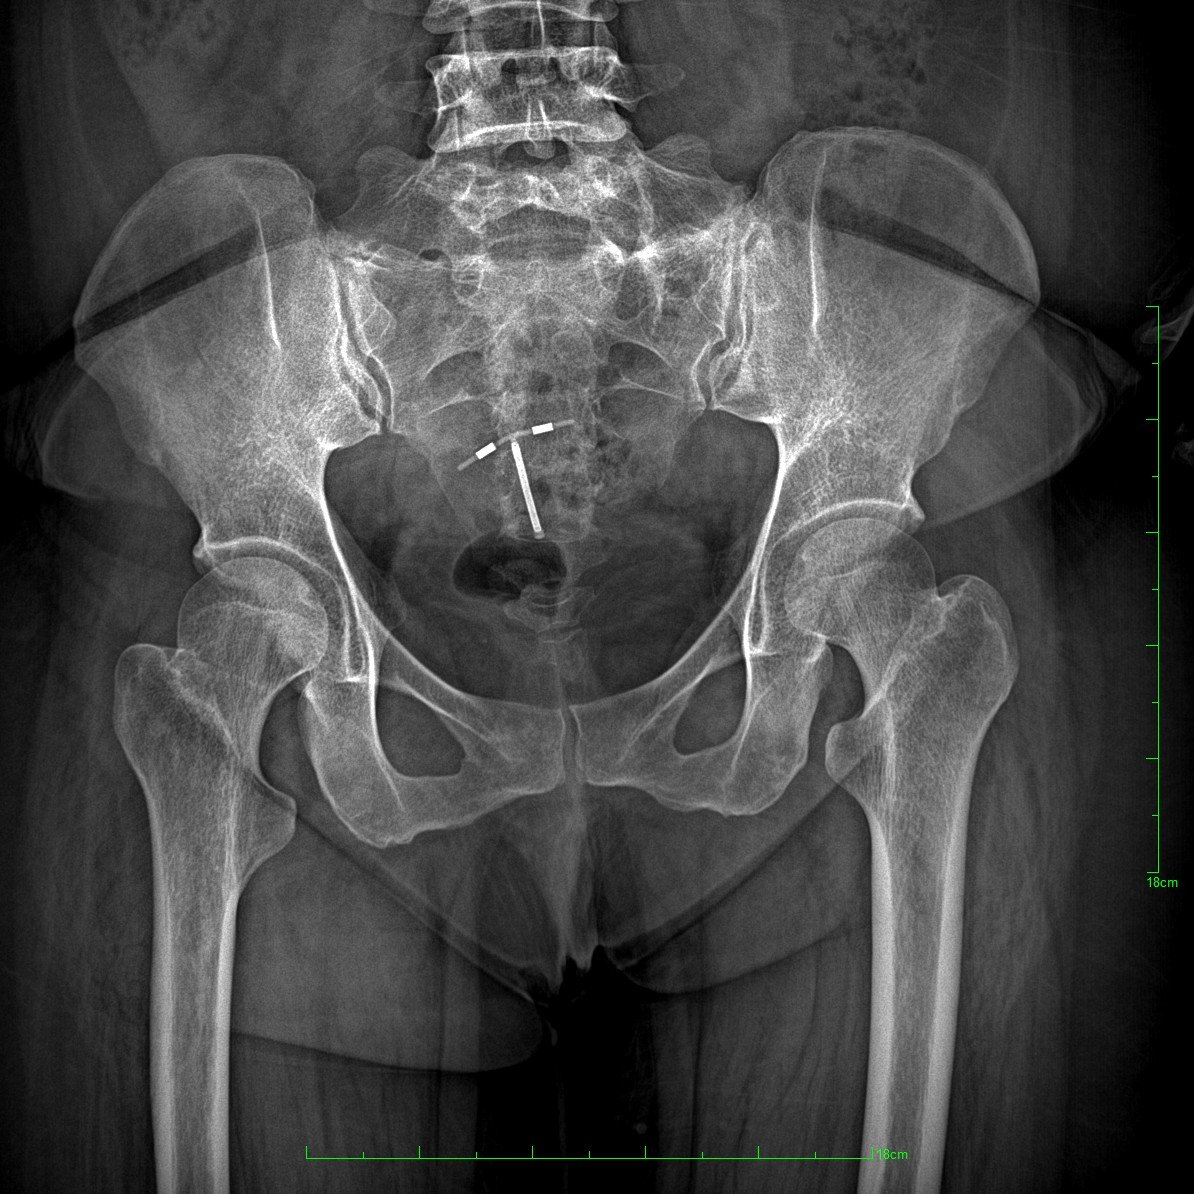

Radiografía Pulsada DFRP: Clave en Traumatología Moderna

DFRP para la Traumatología: Innovación en Diagnóstico Traumatológico con el Vulcan 65 LLM RADIOLOGIA Radiografia…